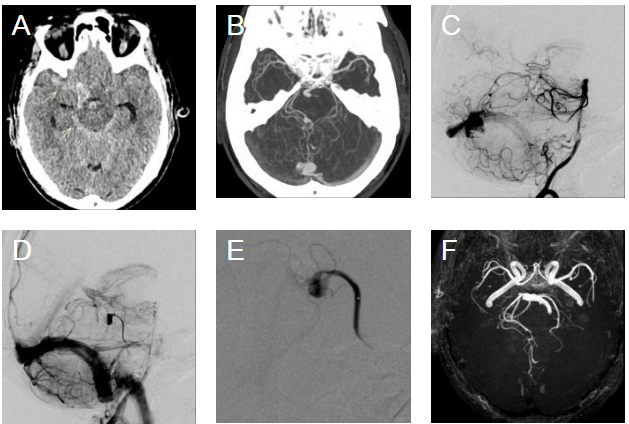

轴向NECT扫描(A)显示蛛网膜下腔出血

伴动脉瘤样改变。轴向CT血管造影

-最大密度投影重建(MIP CTA reformat )(B)显示右侧小脑上动脉存在梭形远端动脉瘤,伴有蚓部血管扩张。动脉期的侧位片(C)和左椎动脉造影(D)显示右侧小脑上动脉和和右侧小脑后下动脉共同供血的蚓部动静脉畸形(AVM)。右侧小脑上动脉后的DSA(E)显示动脉瘤远端闭塞。该患者10年前进行的脑3D-TOF(F)显示右小脑后下动脉和小脑上动脉供血的动静脉畸形,无相关动脉瘤。

诊断:蚓部动静脉畸形主干供血动脉夹层动脉瘤